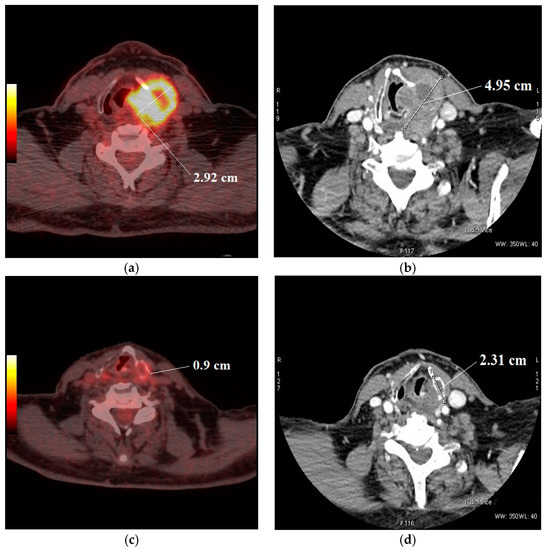

2.4. Image Interpretation